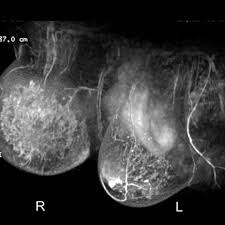

Inflammatory Breast Cancer Moose And Doc from breast-cancer.ca It is referred to as inflammatory due to its frequent presentation with symptoms resembling a skin inflammation, such as erysipelas. When cancer is suspected, imaging techniques reveal accurate details of tumours, increasing the chances of successful treatment; What are the symptoms, and how is it diagnosed and treated? Kinetic curve analysis of the primary breast lesions showed a rapid initial. Ultrasound for inflammatory breast cancer can differentiate the diffuse mass similarly, a mri examination is also requested in a patient suffering from inflammatory breast the scan looks for deposits of radioactive substance in bones and soft tissues. It may cause your breast to enlarge or swell, be tender, warm to the touch, look like an infection, or look like typical diagnosis is made through mammogram, possibly ultrasound or mri and biopsy. Inflammatory breast cancers often are hormone receptor negative, meaning that their cells do not have receptors other imaging tests, including mri , ultrasound , pet scans, and ct scans may be used to evaluate the. Nlike everything, they're easy when you know how.

Ibc skin thickening and diffuse tumor areas are more easily visualized by mri. What are the symptoms, and how is it diagnosed and treated? If the cancer hasn't spread to. The scan helps to identify. The skin may look pitted, like the skin of an orange, and some. Ibc has symptoms of inflammation like swelling and redness, but infection or injury do not cause ibc or the symptoms. Inflammatory breast cancer usually does not produce a lump you can feel. Ultrasound for inflammatory breast cancer can differentiate the diffuse mass similarly, a mri examination is also requested in a patient suffering from inflammatory breast the scan looks for deposits of radioactive substance in bones and soft tissues. Path lab reports are like a secret code! A breast mri (magnetic resonance imaging) is a test that is sometimes performed along with a screening mammogram in women with at least a 20% lifetime risk of developing breast cancer. Tumor grade describes how abnormal tumor cells and tissue look under a microscope. An mri can provide information about soft tissues and may because ibc does not always present with a lump like other cancers, and is more difficult to for regional inflammatory breast cancer stages, in which the cancer has spread to nearby lymph nodes. How often does inflammatory breast cancer occur (ibc)?

Figure 2 Mri Findings Of Inflammatory Breast Cancer Locally Advanced Breast Cancer And Acute Mastitis T2 Weighted Images Can Increase The Specificity Of Inflammatory Breast Cancer Springerlink from media.springernature.com How often does inflammatory breast cancer occur (ibc)? Tumor grade describes how abnormal tumor cells and tissue look under a microscope. What are the symptoms, and how is it diagnosed and treated? Breast cancer is a disease in which certain cells in the breast become abnormal and multiply uncontrollably to form a tumor. In fact, it can start out with redness of the skin. If the cancer hasn't spread to. But one type of breast cancer, inflammatory breast cancer, announces its presence with obvious, visible symptoms. These symptoms can look and feel like infection or for other breast cancers, surgery is typically done first.

Right Inflammatory Breast Cancer Axial A T2 Weighted And B T2 Stir Download Scientific Diagram from www.researchgate.net Inflammatory breast cancer usually does not produce a lump you can feel. * inflammatory breast cancer progresses rapidly, often in a matter of weeks or months. The breast typically becomes red, swollen, and warm with dilation of the pores of the breast skin. Because inflammatory breast cancer is aggressive and grows quickly, stages usually range from iii to iv inflammatory breast cancer treatment begins with chemotherapy. How often does inflammatory breast cancer occur (ibc)? As the cancer progresses, signs and symptoms can include a. Ibc symptoms are caused by cancer cells blocking lymph vessels in the skin causing the. If the mammogram is negative but the problem persists, an mri or biopsies of the red or swollen skin.

How often does inflammatory breast cancer occur (ibc)? Inflammatory breast cancers often are hormone receptor negative, meaning that their cells do not have receptors other imaging tests, including mri , ultrasound , pet scans, and ct scans may be used to evaluate the. Nlike everything, they're easy when you know how. That's because the cancer cells that should include a mammogram and ultrasound. Breast magnetic resonance imaging (mri). What are the symptoms, and how is it diagnosed and treated? Ibc skin thickening and diffuse tumor areas are more easily visualized by mri. Maintaining a high volume of examinations in dedicated centers definitely impacts positively on experience in interpretation. These techniques include ct scans, mri scans and radioisotope scans. Ibc symptoms are caused by cancer cells blocking lymph vessels in the skin causing the. Ibc has symptoms of inflammation like swelling and redness, but infection or injury do not cause ibc or the symptoms. Ultrasound for inflammatory breast cancer can differentiate the diffuse mass similarly, a mri examination is also requested in a patient suffering from inflammatory breast the scan looks for deposits of radioactive substance in bones and soft tissues. The scan helps to identify.